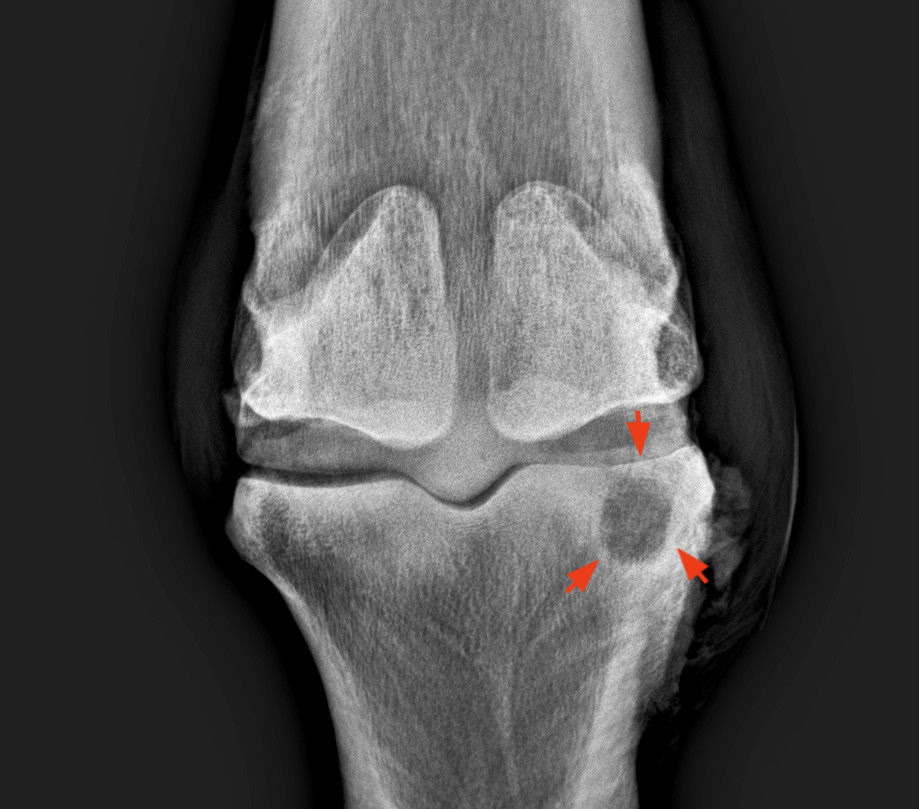

Csontciszta

A csontállomány csökkenése lehet egy körülírt csontciszta (ami leggyakrabban trauma következménye) vagy a csont oldódása (osteolysis), aminek a hátterében leggyakrabban csontgyulladás áll (osteomyelitis).